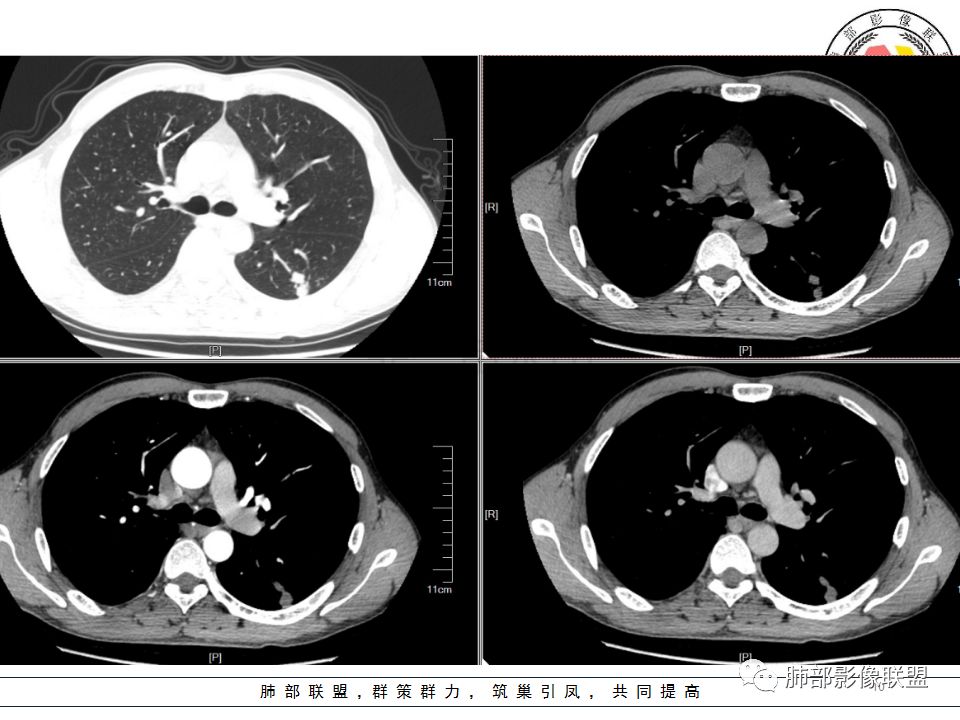

左肺下叶背结节丶融合趋势,形态较单一,平直,无胸膜凹陷,目测轻强化,有支气管爬行丶子灶。诊断:TB>pC>腺癌。

左肺下叶结节,边缘平直为主,部分膨隆,卫星病灶,似乎无强化,糊墙,胸膜下脂肪间隙增宽,结核可能性大,腺癌待排。

左肺下叶背段孤立结节,长轴与胸膜平行,支气管近端截断,刀削平直,糊墙,卫星灶轻强化,考虑TB。

左肺下叶背段小结节 ,糊墙 ,胸膜外脂肪间隙增宽 ,引流支气管壁厚 ,有爬行征 ,病灶无明显强化,考虑结核可能。

考虑结核,左肺下叶病灶,强化不明显,胸膜反应性增厚,有卫星灶,强化不明显。

病史:男,50岁,胸痛15天,无抽烟;胸膜下病灶,有可能相关;

影像:病灶不规则,形态奇特,矢状位可能看到病灶的真实形态;上面近端病灶似乎与主病灶不相连续,多病灶?内侧似乎小花小草,疑为卫星灶;胸膜下病变,与胸膜关系不密切,胸膜线状强化;强化方式渐进性,感觉不均匀,也许是伪影;病灶凹陷平直不膨隆,考虑良性。诊断:结核;鉴别:腺癌(近胸膜端三个胸膜反应凹,偏上部层面毛刺不能除外,但其他地方没有,整体收缩力还比较弱,无钙化,考虑没有形成钙化和纤维化。

男性,胸疼,左肺下叶背段结节,边缘光滑,有平直收缩,轻度延迟强化?胸膜肥厚,有轻度胸膜牵拉,周围有卫星灶,考虑炎性病变,结核,隐球可能性大。鉴别腺癌。

左肺下叶背段结节,边缘较光整,平直,近端支气管未见明确截断征象,沿支气管走行,临近胸膜局限性增厚,增强目测未见明确强化,周围见稀疏小树芽分布,整体考虑良性病变,结核放前考虑。

男,50岁,左肺下叶结节影,似乎两个结节,相邻,上面一个偏内,有分叶,下面一个偏外,胸膜下,内侧有稍增厚的支气管影,并且支气管进入病灶内,周围有更小卫星灶,外侧有胸膜增厚,糊墙。总的来说,考虑炎性病灶,结核可能性最大。但靠内侧的结节有恶性特征,腺癌待排。

50岁男性,吸烟,胸痛15天。左肺下叶胸膜下结节,边缘平直为主,部分膨隆,但似乎呈山丘,沿支气管爬行,周围是卫星灶还是小花小草,考虑恶性,小细胞癌可能性大,结核待排。

左肺下叶背段结节,边缘光滑,有平直收缩,强化不明显,胸膜肥厚,有轻度胸膜牵拉,周围有卫星灶,考虑感染性病变,结核首选。

左肺下叶背段结节,形态近似两个结节融合或靠近,沿支气管走行分布,近侧支气管内见条状软组织,增强未见明确强化,周围见小树芽,首先考虑结核,鉴别小。

患者中年男性,因胸痛半月入院。查血常规、凝血功能、肾功能正常。有抽烟史。胸部CT:左肺下叶背段胸膜下与胸膜垂直长条形不规则病灶,支气管爬行改变,边缘欠清楚,部分层面呈葫芦样见血管集束征、周围点状卫星灶,增强无明显强化,左肺门淋巴结肿大。综合常规结核可能性大,其次小细胞肺癌。鉴别其他。

左肺下叶病变,边缘平直,似有U形凹陷,树芽及卫星病灶,支气管爬行征?无明显强化,考虑结核。

左肺下叶背段近胸膜下结节,部分边缘平直并可见卫星灶,增强后强化不明显,首先考虑结核。

中年男性,左肺下叶背段结节,内可见支气管充气征,周围有晕,周围有结节,局部胸膜增厚,可见脂肪间隙。考虑良性病变可能,隐球?,鉴别结核;病灶有沿支气管生长趋势,气道阻塞,经皮肺穿除外肺癌。

中年男性,胸痛,吸烟史。左肺下叶背段结节,边界清楚,局部见小毛刺及胸膜牵拉,部分层面成葫芦形,局部与胸膜宽基底相贴,邻近胸膜增厚。近端支气管达病灶边缘处,似略增厚。周围见少量卫星微结节及树丫。增强扫描无强化。考虑:1,结核:支持点有发病部位,邻近卫星灶及树丫,近病灶边缘支气管壁似略增厚,邻近胸膜增厚。不支持点,引流支气管壁增厚范围不够长。2,小细胞癌:支持点有局部葫芦形,似沿支气管向肺门区扩展。3,腺癌:支持点有毛刺和胸膜牵拉,当然结核也可以有这两个征象。不支持点有无强化。